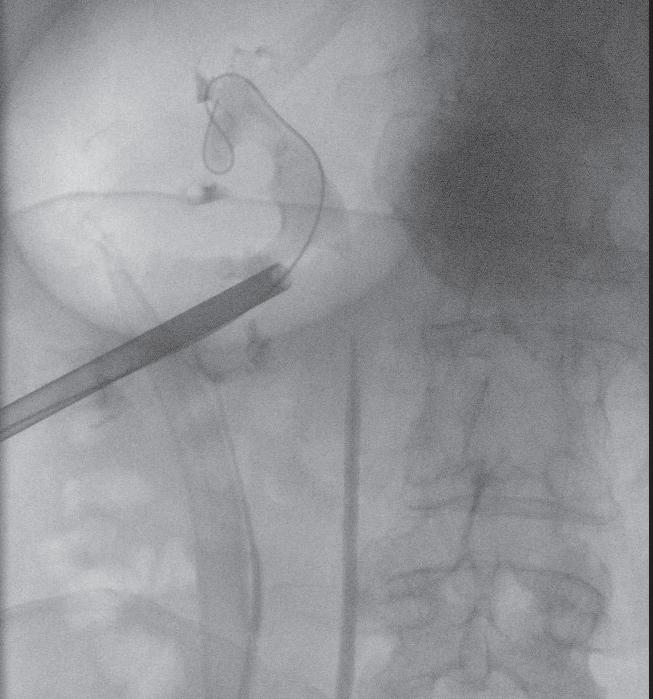

Miniperc 1: Kontrastmitteldarstellung der Kelche und des Nierenbeckens sowie Punktion.

Miniperc 2: Zugang mittels Einschrittdilatators.

Miniperc 3: Finales Bild mit antegrader DJ-Anlage.

tungsrisiko. Ein kleinerer Durchmesser bedeutet aber auch längere OP-Zeiten. Grundsätzlich wird der Zugang durch die Haut mittels einer entsprechenden Nierenpunktion gelegt (siehe Abbildung, S. 23). Die exakte Positionierung der Punktionsstelle sollte mittels Punktionssonografie und idealerweise kombiniert mit einer Röntgendurchleuchtung erfolgen. Dadurch können die Lage des Konkrements und die Beschaffenheit der Niere besser beurteilt bzw. eingeschätzt werden.9 In der Folge werden die Steine unter Verwendung eines Lasers oder eines Lithoklasten (unter Druckluftwirkung können Steine zerkleinert werden) fragmentiert und die einzelnen Konkremente ausgespült. Dabei zeigten sich bereits früh in der Anwendung dieser Operationstechnik vielversprechende Ergebnisse, sodass die Komplikationsrate mittlerweile überschaubar und die Steinfreiheitsrate hoch ist.10